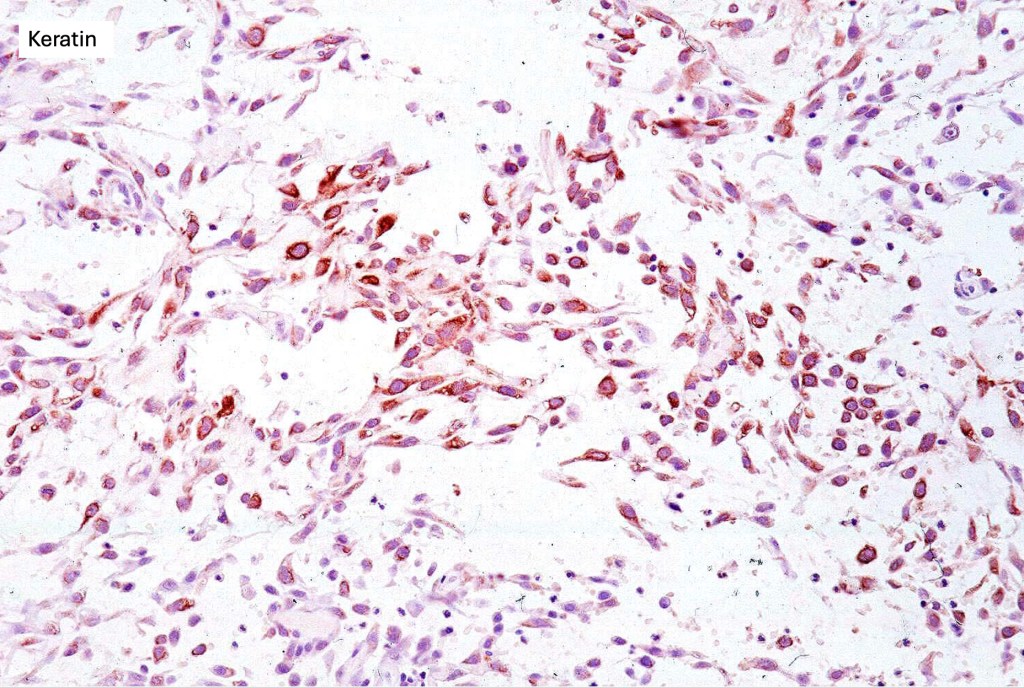

Histological features

•Generally, tumors are well differentiated although they can later develop a more poorly differentiated morphology

•Keratoses may represent a precursor & sometimes histological distinction between very marked epidermal hyperplasia (pseudoepitheliomatous) and early SCC can be problematical (personal observation)